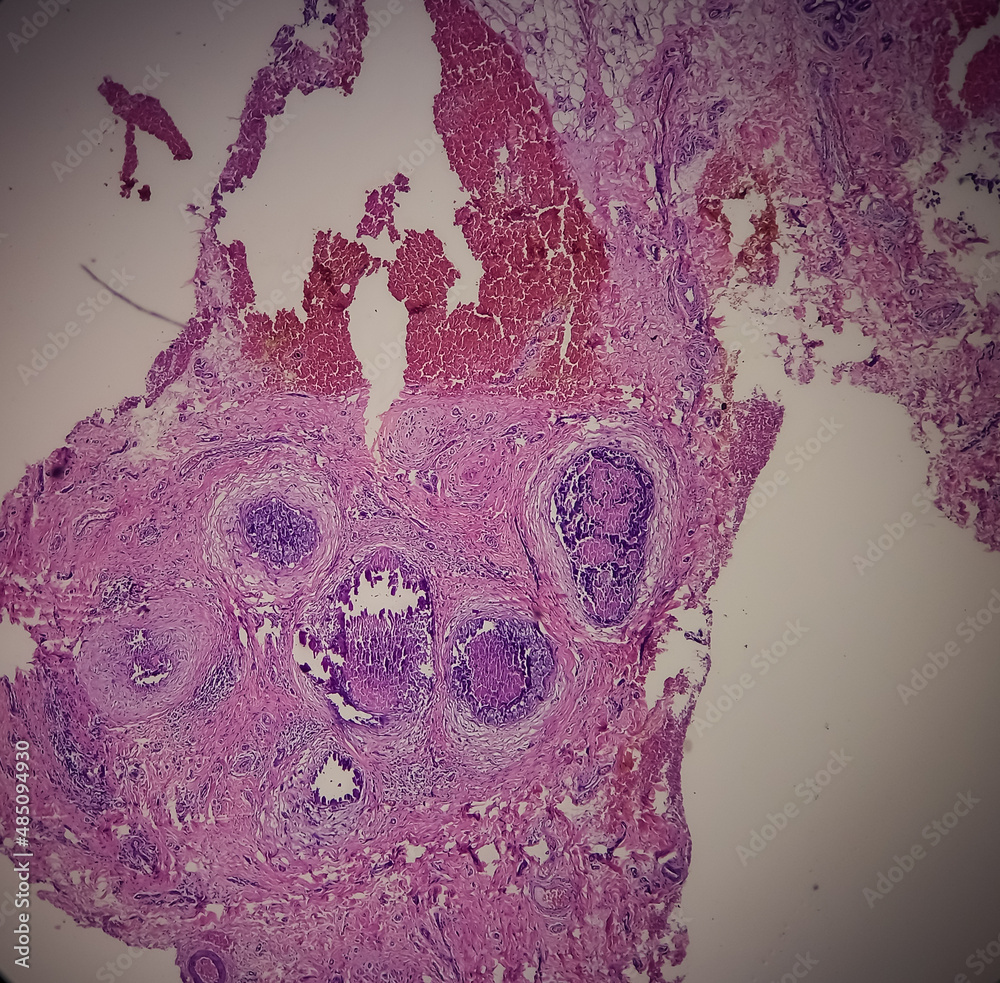

Nipple (biopsy) Invasive squamous cell carcinoma of nipple Paget's Disease Of The Nipple Biopsy paget's disease of the breast is an uncommon manifestation of underlying breast cancer in postmenopausal female patients. a biopsy is used to confirm a suspected diagnosis of paget's disease of the nipple. There are several types of nipple biopsy,. A small tissue sample (punch biopsy of the. paget disease of the breast is diagnosed by a biopsy,. Paget's Disease Of The Nipple Biopsy.

Nipple ulcer biopsy Paget's disease of the nipple, microscopic image Paget's Disease Of The Nipple Biopsy paget's disease of the breast typically affects postmenopausal women and is associated with an underlying. a skin biopsy is often used to confirm a diagnosis of paget's disease of the nipple. paget disease of the breast is diagnosed by a biopsy, removing a small piece of the breast tissue and looking at it closely in. A small. Paget's Disease Of The Nipple Biopsy.

Nipple ulcer biopsy Paget's disease of the nipple, microscopic image Paget's Disease Of The Nipple Biopsy A small tissue sample will be taken from. paget disease of the breast is diagnosed by a biopsy, removing a small piece of the breast tissue and looking at it closely in. a nipple biopsy allows doctors to correctly diagnose paget disease of the breast. There are several types of nipple biopsy,. a biopsy is used to. Paget's Disease Of The Nipple Biopsy.